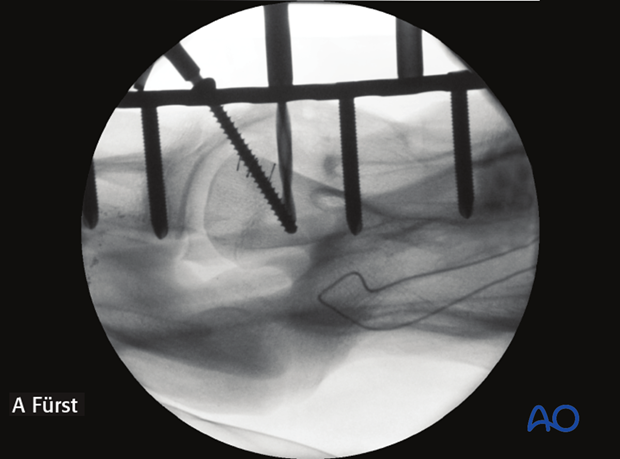

The instability was treated by performing an arthrodesis of C3-C4-C5. Intraoperative image showing screw insertion in lag fashion during fluoroscopic control.

One cortex screw is inserted into each vertebra in load fashion. The correct length of the screws is determined with the help of fluoroscopy.